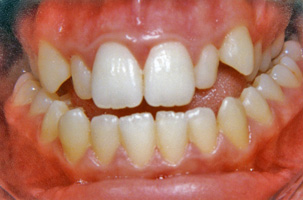

3. Μεταχειρουργική ορθοδοντική θεραπεία:

Αφού τελειώσει η περίοδος της ακινητοποίησης, ο ασθενής επιστρέφει στον ορθοδοντικό ο οποίος πλέον ασχολείται με την μεταχειρουργική ορθοδοντική διευθέτηση των δοντιών. Καθώς έχει ήδη αποκατασταθεί η τελική καλή σχέση των γνάθων μεταξύ τους, είναι πλέον δυνατές και κάποιες μικρομετακίνησεις ακριβείας των δοντιών προκειμένου να επιτευχθεί μια σταθερή και λειτουργική σύγκλειση. Η διάρκεια της μεταχειρουργικής ορθοδοντικής θεραπείας ποικίλλει από 4-12 μήνες.

Οι μεικτές αυτές θεραπείες είναι εξαιρετικά εντυπωσιακές δεδομένου ότι ευνοούν όχι μόνο το στόμα και το χαμόγελο αλλά και το πρόσωπο συνολικά. Οι ασθενείς διανύουν ένα μακρύ δρόμο αλλά το τελικό αποτέλεσμα επηρεάζει τόσο θετικά την ζωή τους που αποζημιώνονται.